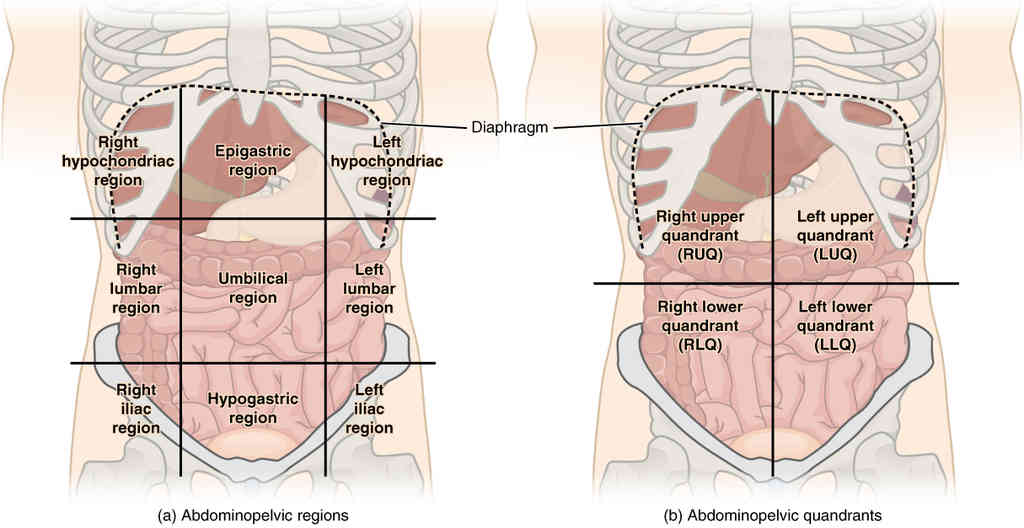

This page is under construction. For now, it is just a resource of the images found in the OpenStax Anatomy and Physiology Handbook. It wil slowly change into a revision tool. Each slide has a number. Use this to refer to the slide. When completed, it will have an unlabelled section, with labelled slides in parallel. On the unlabelled slides, write your answer and use the labelled slide to assess yourself. Keep track by also noting the number on each slide. Improvement at each attempt is important, more so than full marks on a first attempt.